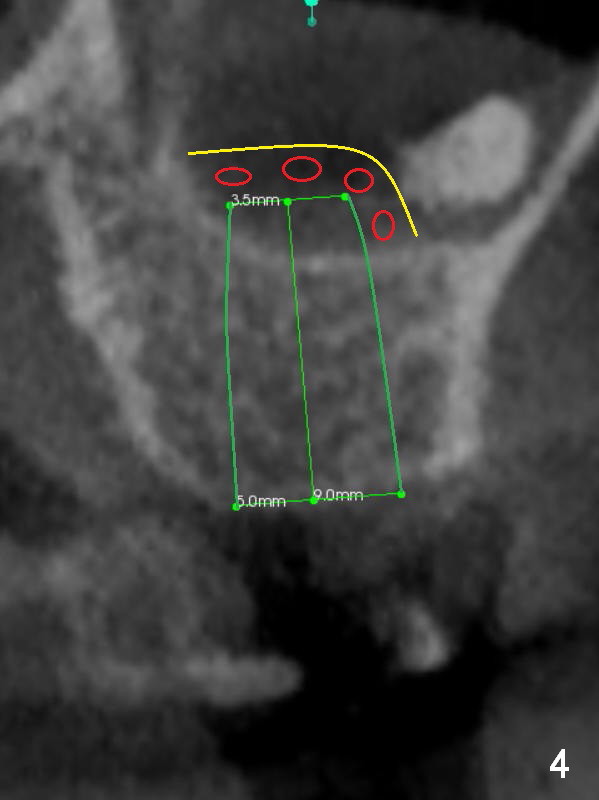

CT shows a residual root in the left maxillary sinus. In order not to re-infect the sinus, an implant at the site of #14 should not enter the sinus (Fig.2) or enters the sinus with bone graft (Fig.3,4 red circles) and more importantly PRF membrane (yellow).